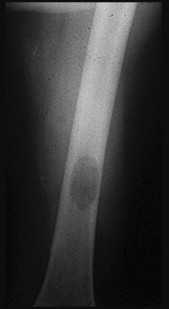

Question 3:

A 55-year-old male undergoes excision of a large cartilaginous tumor of the proximal femur. Molecular analysis of the tumor reveals a mutation in the isocitrate dehydrogenase 1 (IDH1) gene. This mutation is a hallmark of and most frequently associated with which of the following conditions?

Correct Answer: Ollier disease

Explanation:

Mutations in the IDH1 and IDH2 genes are heavily implicated in the pathogenesis of cartilaginous tumors. Somatic mosaic mutations in these genes are found in over 80% of patients with Ollier disease and Maffucci syndrome, both of which are forms of enchondromatosis. Multiple Hereditary Exostoses is associated with EXT1/EXT2 mutations. McCune-Albright is associated with GNAS mutations. NF1 is associated with the neurofibromin gene.